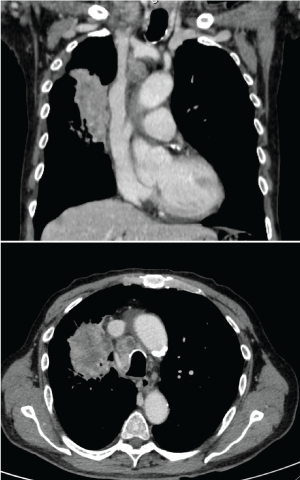

A new panoramic radiography revealed the extensive advance of the osteolytic process that affects the right mandibular condyle. A craniofacial CT demonstrates the total osteolysis of the right temporomandibular region, occupied by a 3.6-2.8 cm mass in the infra temporal fossa and right pterygomaxillary space (Figure 4). Through preauricular end aural approach the lesion is accessed (Figure 5) obtaining an amorphous, solid, not vascularized tissue sample that is sent to differed biopsy; reporting a moderately differentiated adenocarcinoma, characterized by a solid cellular mass that resemble glandular parenchyma with scarce duct-like structures spread all over the tissue (Figure 6). Immunohistochemical analysis mean to find the primary tumor, reveal positive results to Cytokeratin 7 (CK7+), compatible with an adenocarcinoma. At this point, cannot be ruled out the possibility for a salivary gland adenocarcinoma of parotid origin against a possible metastatic adenocarcinoma, of probably lung origin. The Cluster of differentiation 10 (CD10) for renal origin is also requested because of focal areas of clear cells, with negative response. A computed tomography with contrast of abdomen, chest and pelvis is requested, where a large mass of soft tissue density and irregular borders of 6 × 5.5 cm, with necrotic areas inside is observed in the right pulmonary lobe, widely contacting the pleura at the para mediastinal level, remarking multiple pulmonary nodules and regional adenopathy's (paratracheal, subcardial and supraclavicular) (Figure 7).

Figure 7: Chest CT coronal and axial cut. The image shows a large mass of soft tissue density and irregular borders of 6 × 5.5 cm, with necrotic areas inside is observed in the right pulmonary lobe, widely contacting the pleura at the paramediastinal level, ramarking multiple pulmonary nodules and regional adenopathies (paratracheal, subcardial and supraclavicular). View Figure 7